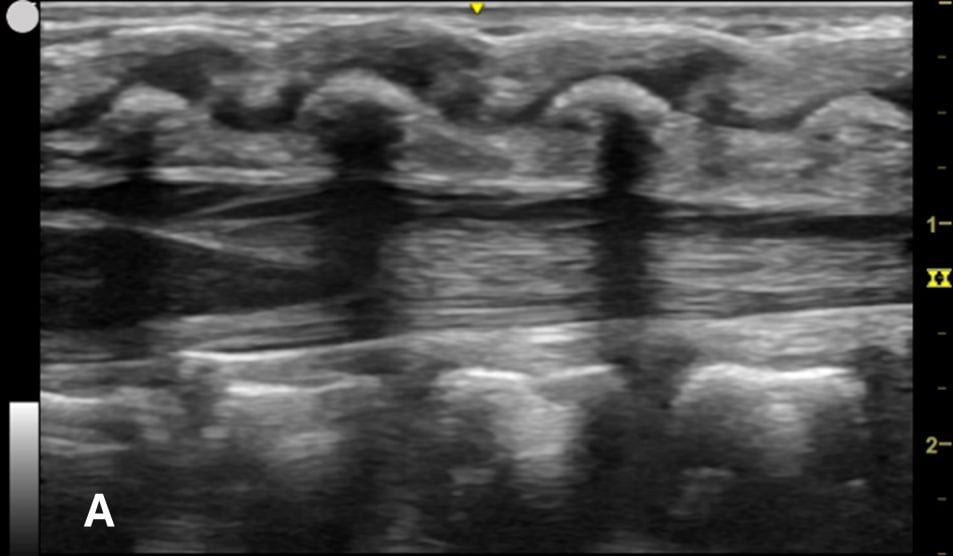

US-assisted LP is performed using the high-frequency linear transducer at the infant’s lower lumbar spine, with the patient either in a lateral recumbent position or an upright sitting position. The standard LP position, in which the neck and hips are flexed, should be used to locate the optimal site for needle insertion. Warm gel should be used during US to provide comfort and reduce the risk of hypothermia in infants. Align the transducer along the spinous process of the lumbar spine above the level of intercristal line to obtain a sagittal view of the spinal canal. The tapered CM is identified, below which any space is safe for needle insertion. The amount of anechoic cerebrospinal fluid (CSF) can be grossly compared in each space to locate the ideal LP site to obtain maximal CSF volume. (Figure 1A-B) The next step is to mark the skin at this optimal intervertebral level using a marking pen. Additionally, we recommend measuring the depth from the skin to the posterior border of the subarachnoid space using calipers, ensuring an angle of entry of 30–45 degrees. (Figure 1C) This allows the proceduralist to more precisely estimate the minimum needle depth needed to reach the subarachnoid space.

Figure 1A - Corresponding US image showing the target area of the lower spinal canal in sagittal/longitudinal view.